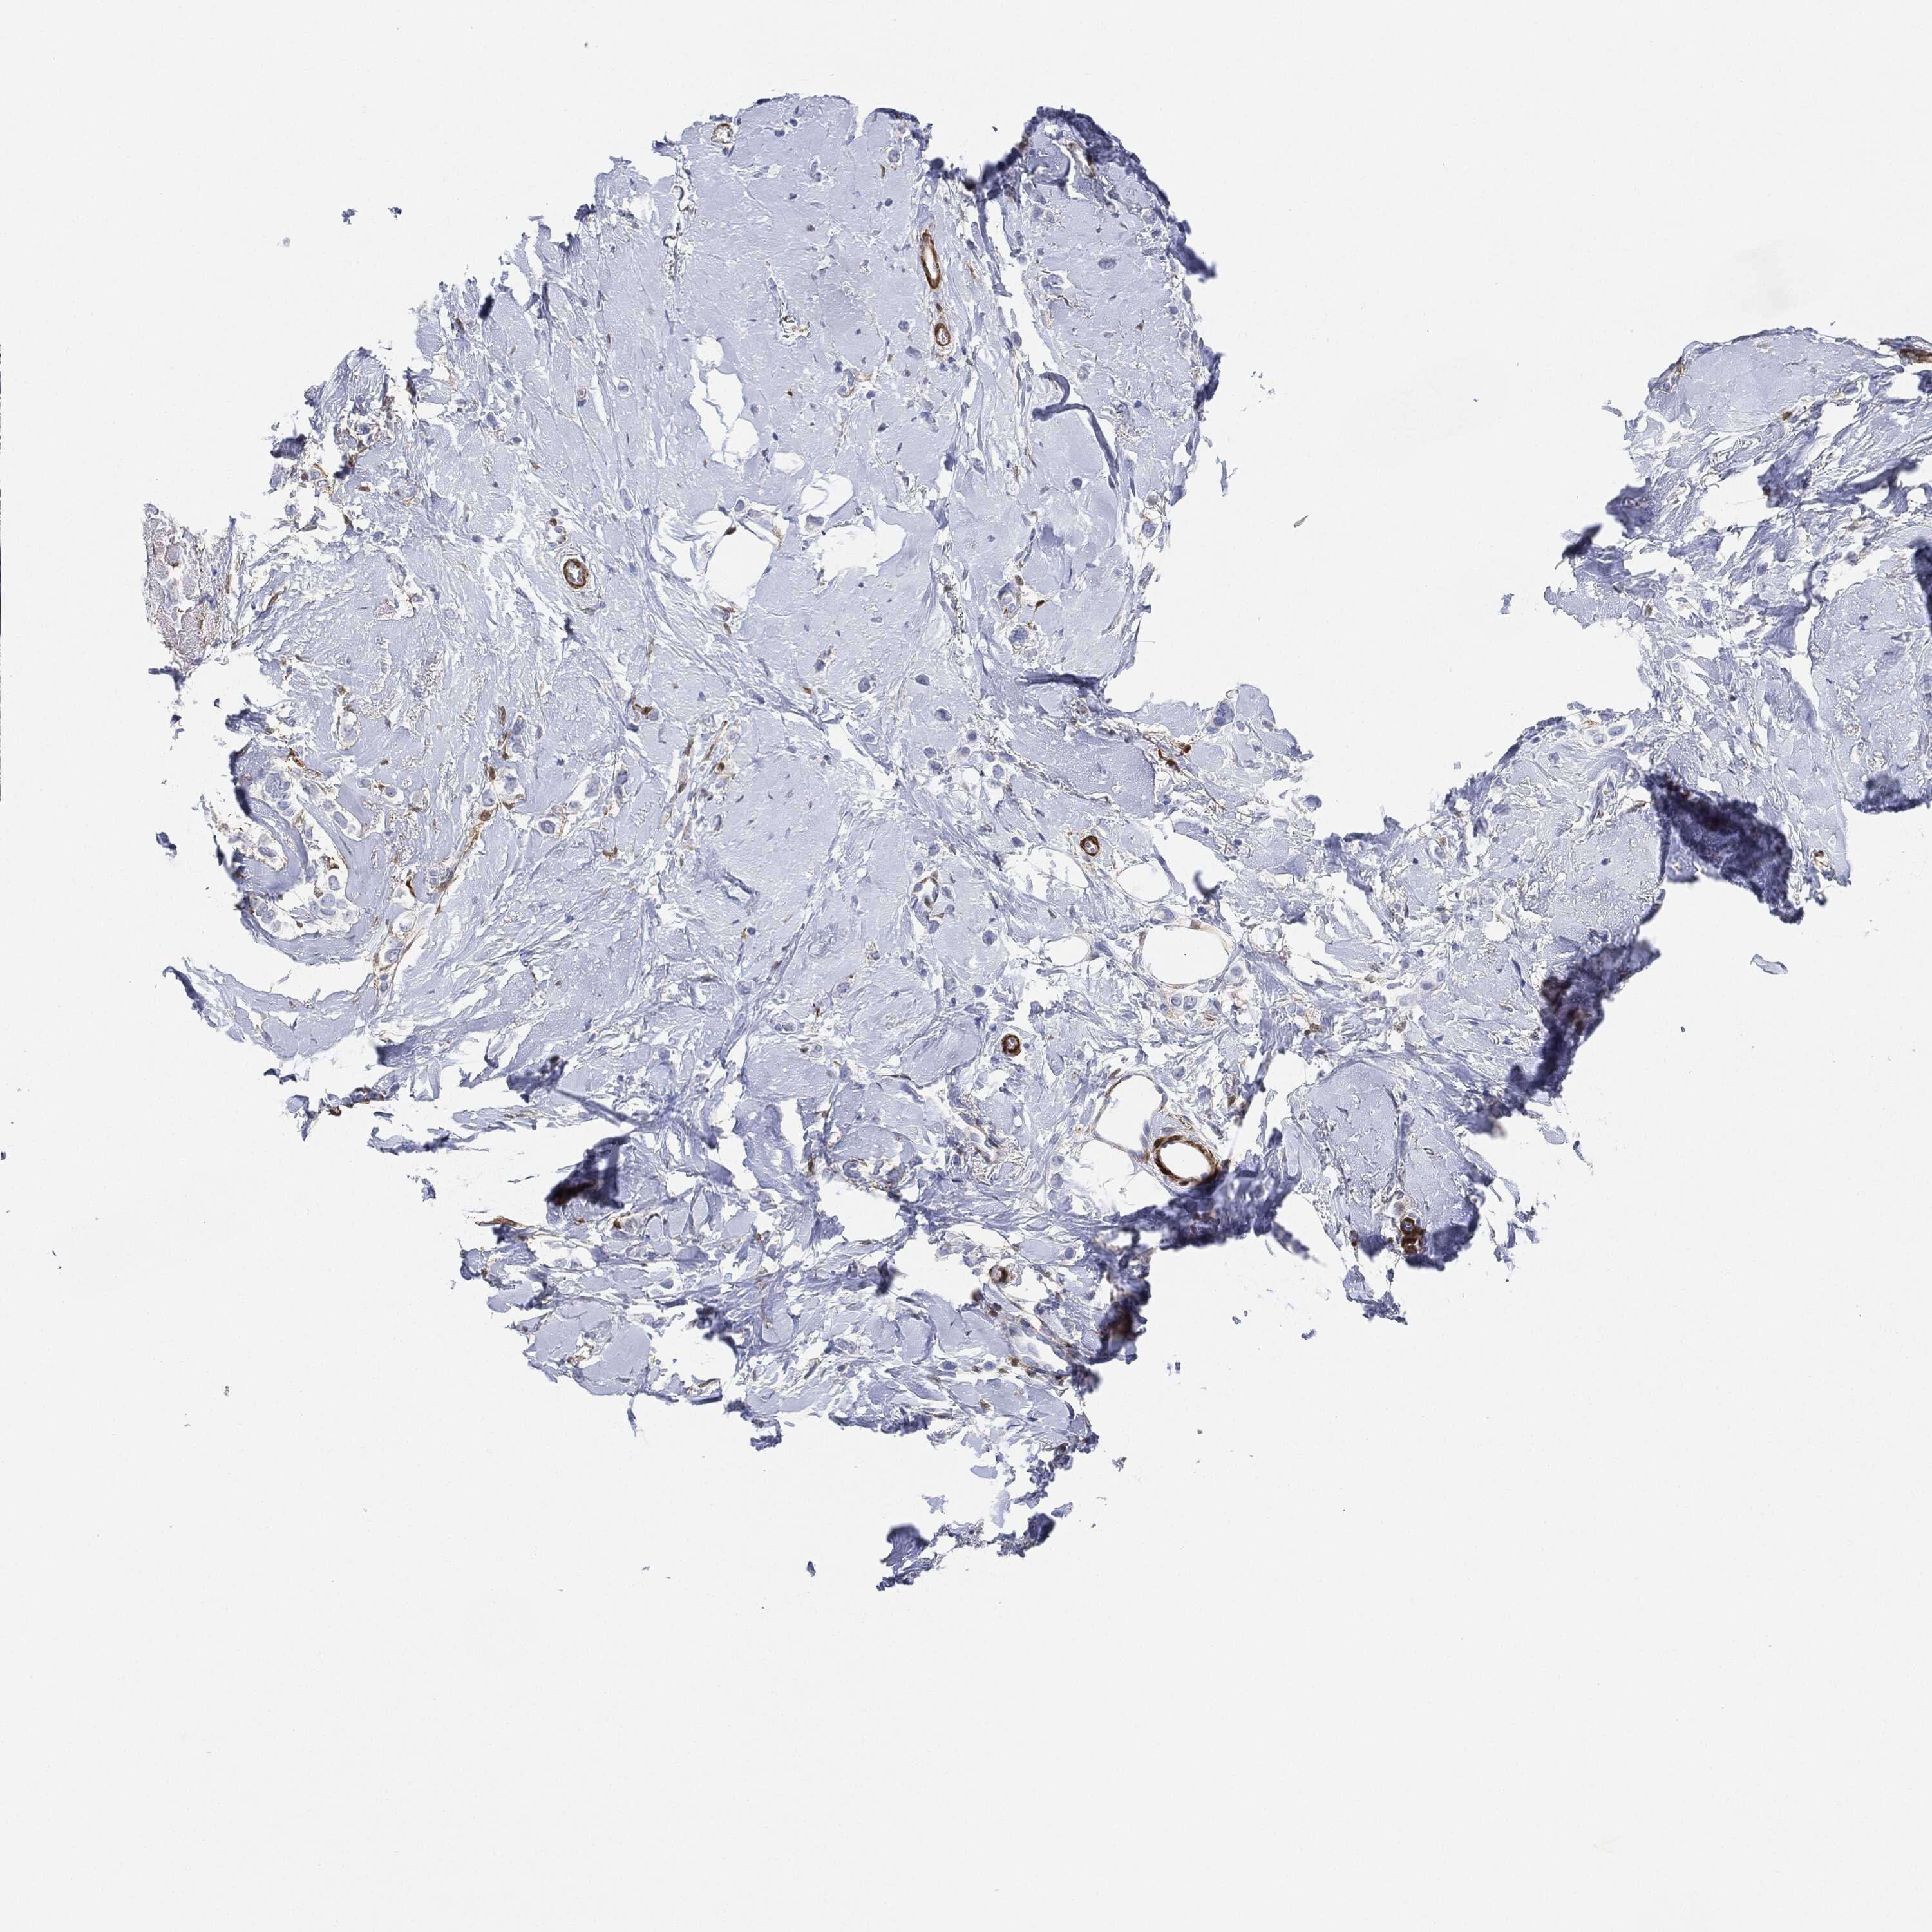

BRCA TCGA BRCA VALIDATION PROTEIN EXPRESSION

ANTIBODIES

AND

VALIDATION